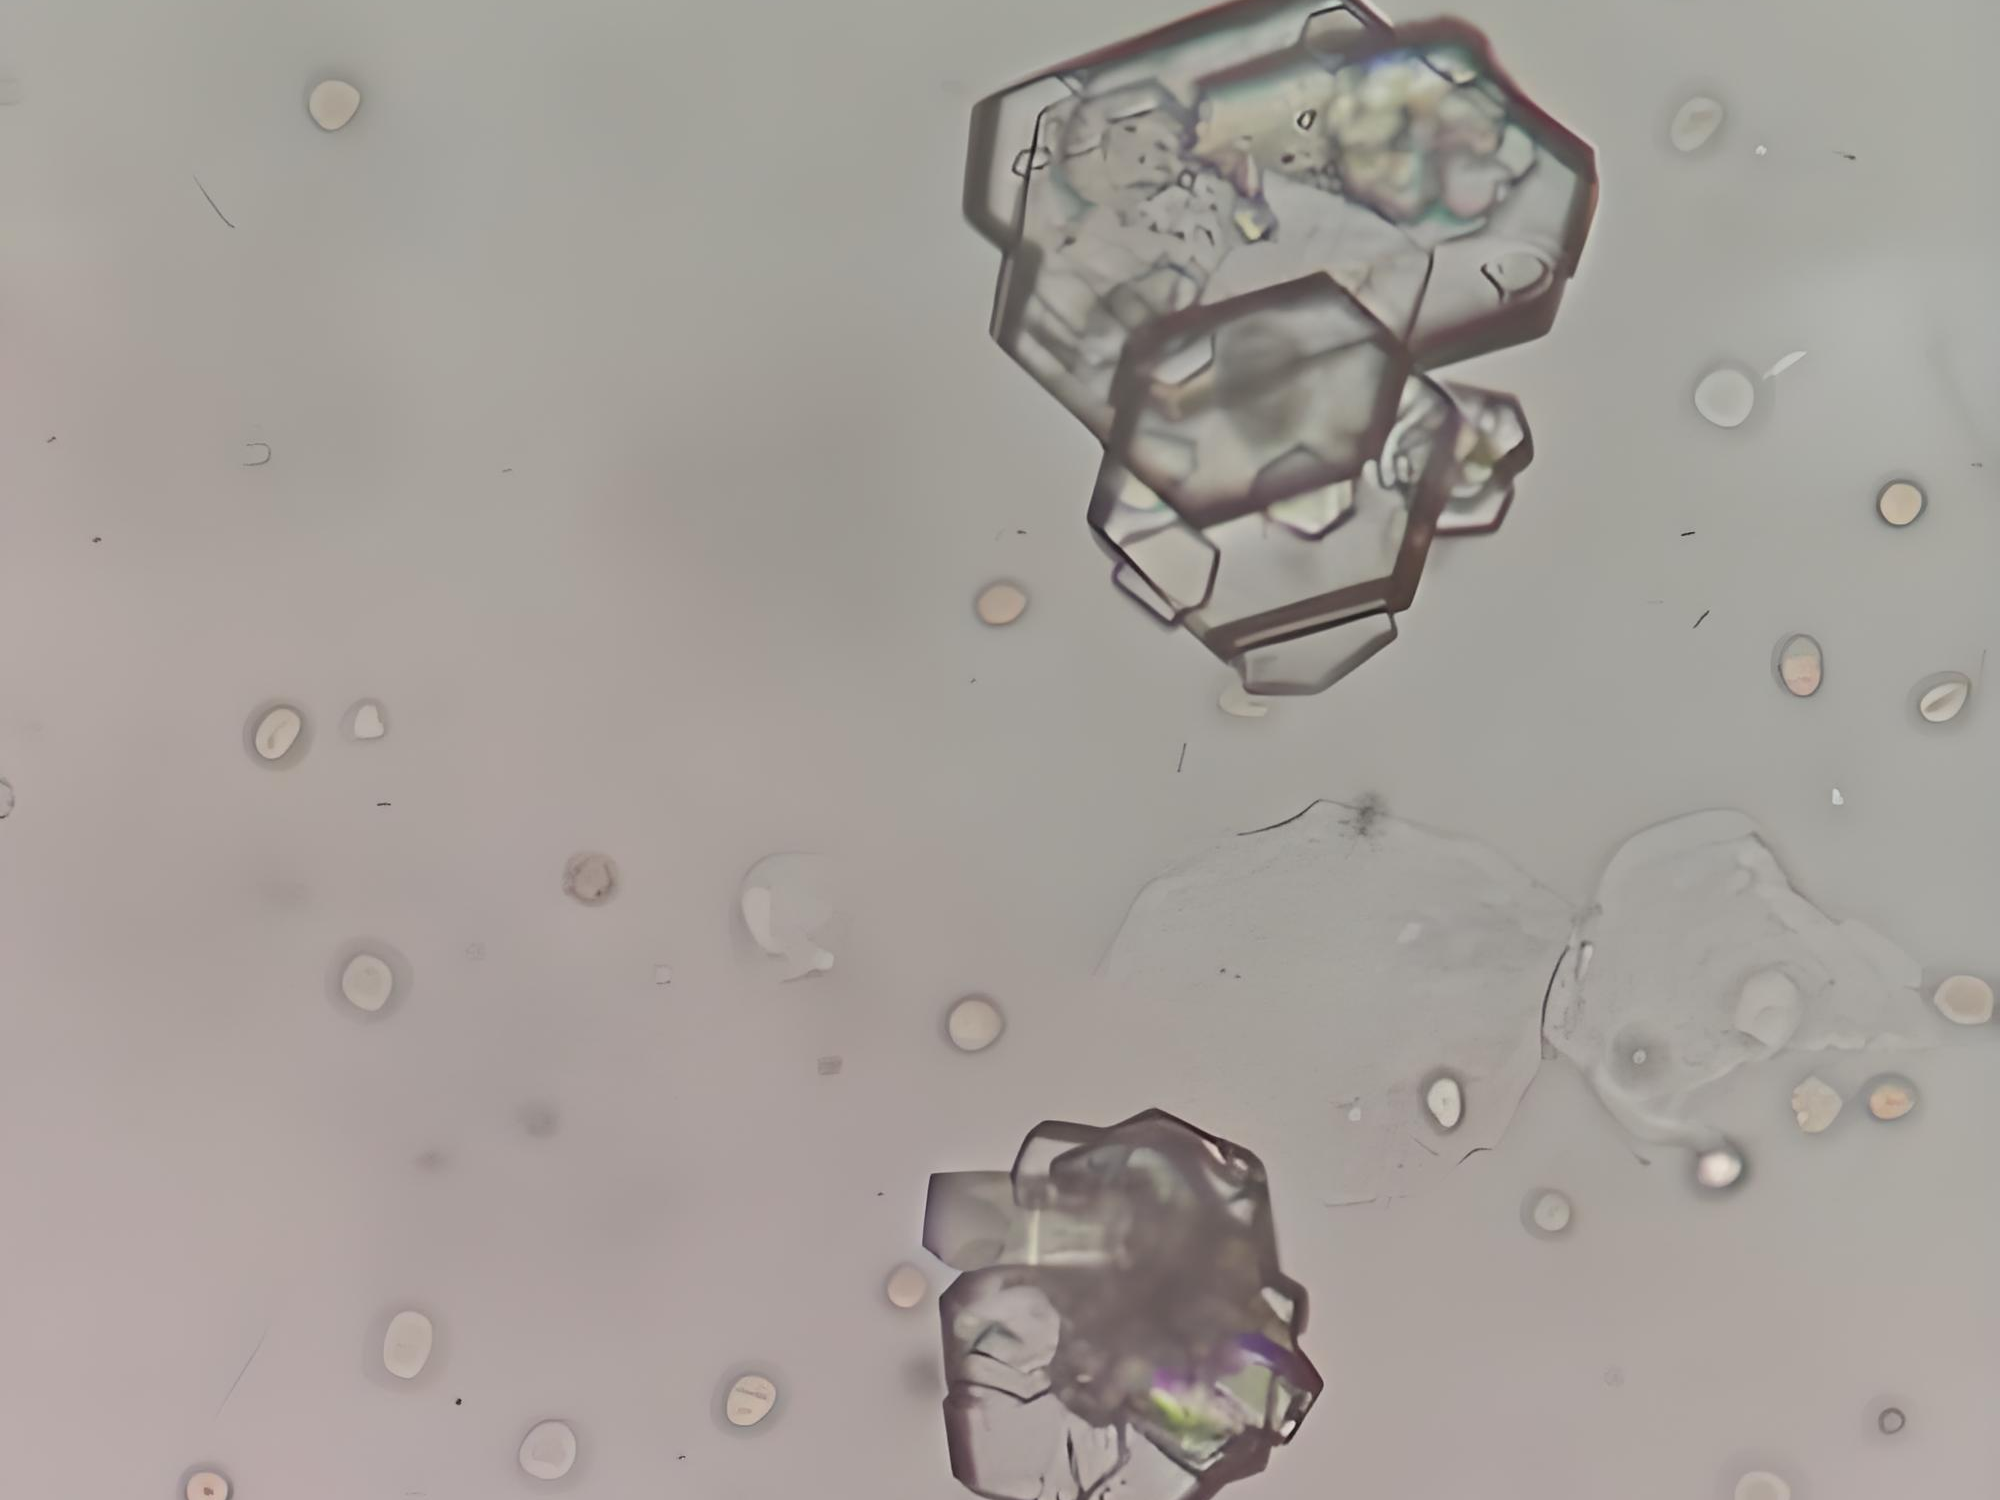

外觀:顏色通常較淺,可呈淡黃色,純胱氨酸成分。顯微鏡下最具特征的是六邊形片狀晶體,這種規整的幾何形態在偏振光顯微鏡下尤為明顯。

奇妙的晶體微觀世界:小小腎結石,顯微鏡下大不同

今天,讓我們通過顯微鏡這個“微觀之眼”,認識一下這些腎臟中的“不速之客”。